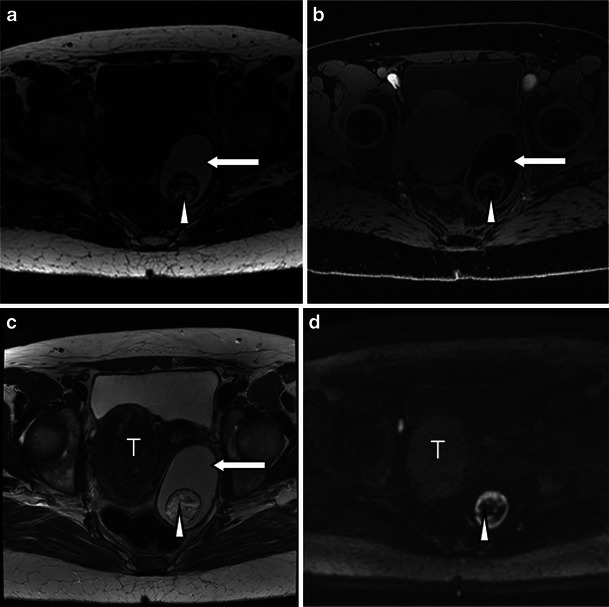

Struma ovarii is a rare type of mature teratoma, but its imaging features are rather distinct. Whilst immature teratomas are known to be predominantly solid with small foci of fat, mature cystic teratomas or dermoid cysts are known to be predominantly cystic, present as a fat-containing mass and are often associated with calcifications as well as an enhancing nodule-forming soft-tissue component [3]. Diagnosis of uncomplicated teratomas using computed tomography (CT) and magnetic resonance (MR) imaging is fairly straightforward because both techniques are highly sensitive in the detection of fat within the tumour, presenting as negative attenuation on CT [7]. On MRI, three methods have been used to distinguish the fatty contents of the mature cystic teratoma from those of endometriomas or other haemorrhagic cysts. First, chemical shift artefact in the frequency encoding direction can be used to detect fat and to distinguish fat from haemorrhage [18]. Second, gradient-echo imaging, using an echo time in which fat and water are in opposed phases, can demonstrate fat–water interfaces and mixtures of fat and water [19]. Third, sequences with frequency-selective fat saturation will suppress the high signal of the intralesional fat in teratomas and help distinguish them from haemorrhagic lesions [3]. MR imaging with this latter technique allows accurate differentiation between teratomas and haemorrhagic cysts and is preferable to the other techniques [3]. The key features of a mature teratoma using water-only and fat-only T1 technique and diffusion-weighted imaging are demonstrated in Fig. 1. Of note is the restricted diffusion present in the sebaceous material within the cyst (Fig. 1).

Fig. 1.

Three-tesla MR images of a mature teratoma or dermoid cyst arising from the left ovary in a 53-year-old patient. The fatty component in the lesion is hyperintense on the 3D-LAVA fat-only T1-weighted image (a) and hypointense on the water-only T1-weighted image (b) (arrows). c T2-weighted high-resolution image shows the fatty component within the lesion to be hyperintense (arrow). The nidus itself contains a fatty component that is also hyperintense on 3D-LAVA fat-only T1-weighted image (a) and hypointense on the water-only T1-weighted image (b) (arrowheads). d Diffusion-weighted image using a b value of 1,200 s/mm2 shows a high signal intensity rim representing restricted diffusion from sebaceous material surrounding the nidus and punctuate areas of restricted diffusion scattered throughout the nidus (arrowhead). The pedunculated uterine fibroid (T) at the level of the right lateral aspect of the uterus presents with typical hypointensity on T2 (c) without associated restricted diffusion (d)